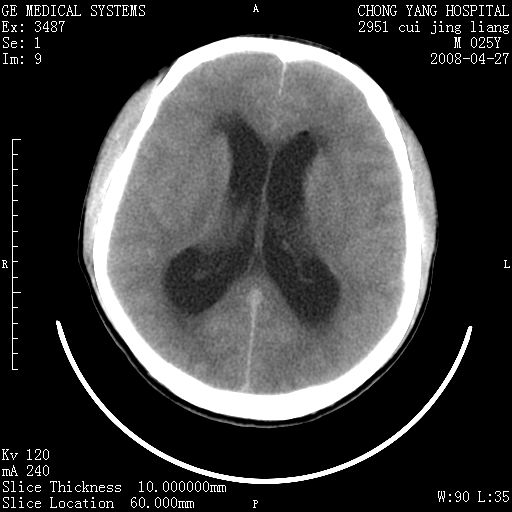

以下是引用余辉在2008-4-27 17:08:00的发言:[br]支持考虑松果体区畸胎瘤伴梗阻性脑积水,左侧室前角还有脂液滴?

以下是引用随光逐影在2008-4-27 20:13:00的发言:[br]1)考虑为:第三脑室后部、松果体区畸胎瘤。2)脑积水(梗阻性)。

以下是引用jinguoji在2008-4-27 23:41:00的发言:[br]考虑松果体区肿瘤引起梗阻性脑积水。